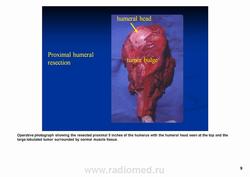

Рентгенологически выявляют в очаге деструкции участки обызвествления в виде крапчатости; кортикальный слой с признаками эрозии со стороны эндоста и истончения; размеры опухоли более 4 см; периостальная реакция слабо выражена или отсутствует; может наблюдаться деструкция кортикальной кости и наличие мягкотканного компонента; в длинных костях локализуется чаще в метафизах и диафизах; интенсивное внутрикостномозговое распространение.